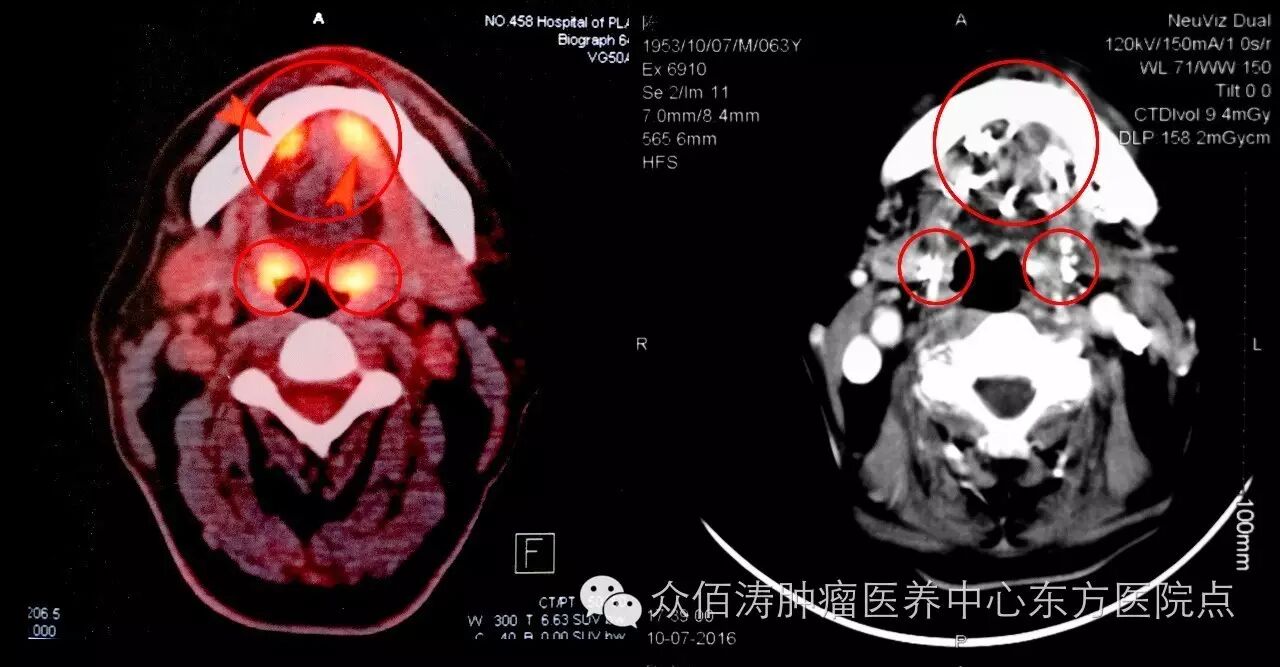

术前/术后CT,肿瘤已完全消除